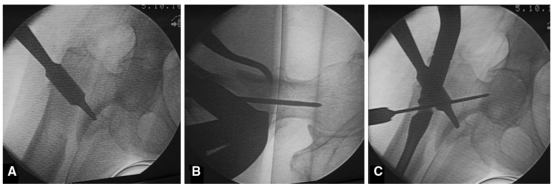

对于复杂的粗隆下骨折和闭合复位不可行或不能接受的骨折,应使用切开复位技术。在这种情况下,为了保存骨折生物学,建议采用微创复位技术。单皮质Schanz钉可以通过皮肤的穿刺切口使用,以便操纵骨折碎片。一个或两个Schanz钉可以通过电钻置入在想要进行复位的骨折块中,并与T形手柄连接用作操纵杆,从而使外科医生能够操纵骨折碎片以获得满意的复位和推进导丝。在进行扩髓之前,应该用C臂机透视检查评估Schanz钉辅助下的骨折复位情况和Schanz钉所处的位置(如图2A-C所示)。这项技术几乎是无创的,可以在扩髓过程和置入髓内钉的过程中保持复位。

图2 A经皮Schanz钉微创复位治疗股骨粗隆下横形骨折;C将Schanz针插入到近端骨折块;C将另一针插入到远端片段以便于复位